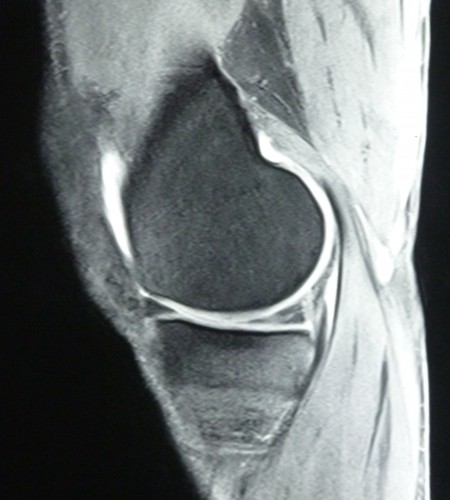

Meniskusriss 2009-1